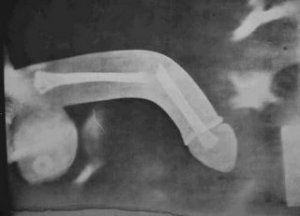

A Sexual Medicine című lapban jelent meg egy tanulmány miszerint azoknak a férfiaknak, akik afférokba keverednek, nagyobb esélyük van a péniszük megtörésére is.

A Marylandi egyetem orvosai felfedezték, hogy azok a pácienseik, akik péniszsérülésekkel keresték fel az intézményt , legtöbb esetben sebtiben elkövetett afférok során szerezték be.

“A pénisz roncsolódása még jellemzőbb a durva, “cowboy szexnél” – teszi hozzá az urológus. – Ha a nő van felül az aktus során, mozgását mindenképp érdemes irányítani, azzal, hogy a stabilizáljuk a medencéjét – fogjuk két oldalról -, nehogy lejjebb csússzon a kelleténél a “lovaglás” közben, mert legtöbbször ez vezet sérüléshez”.